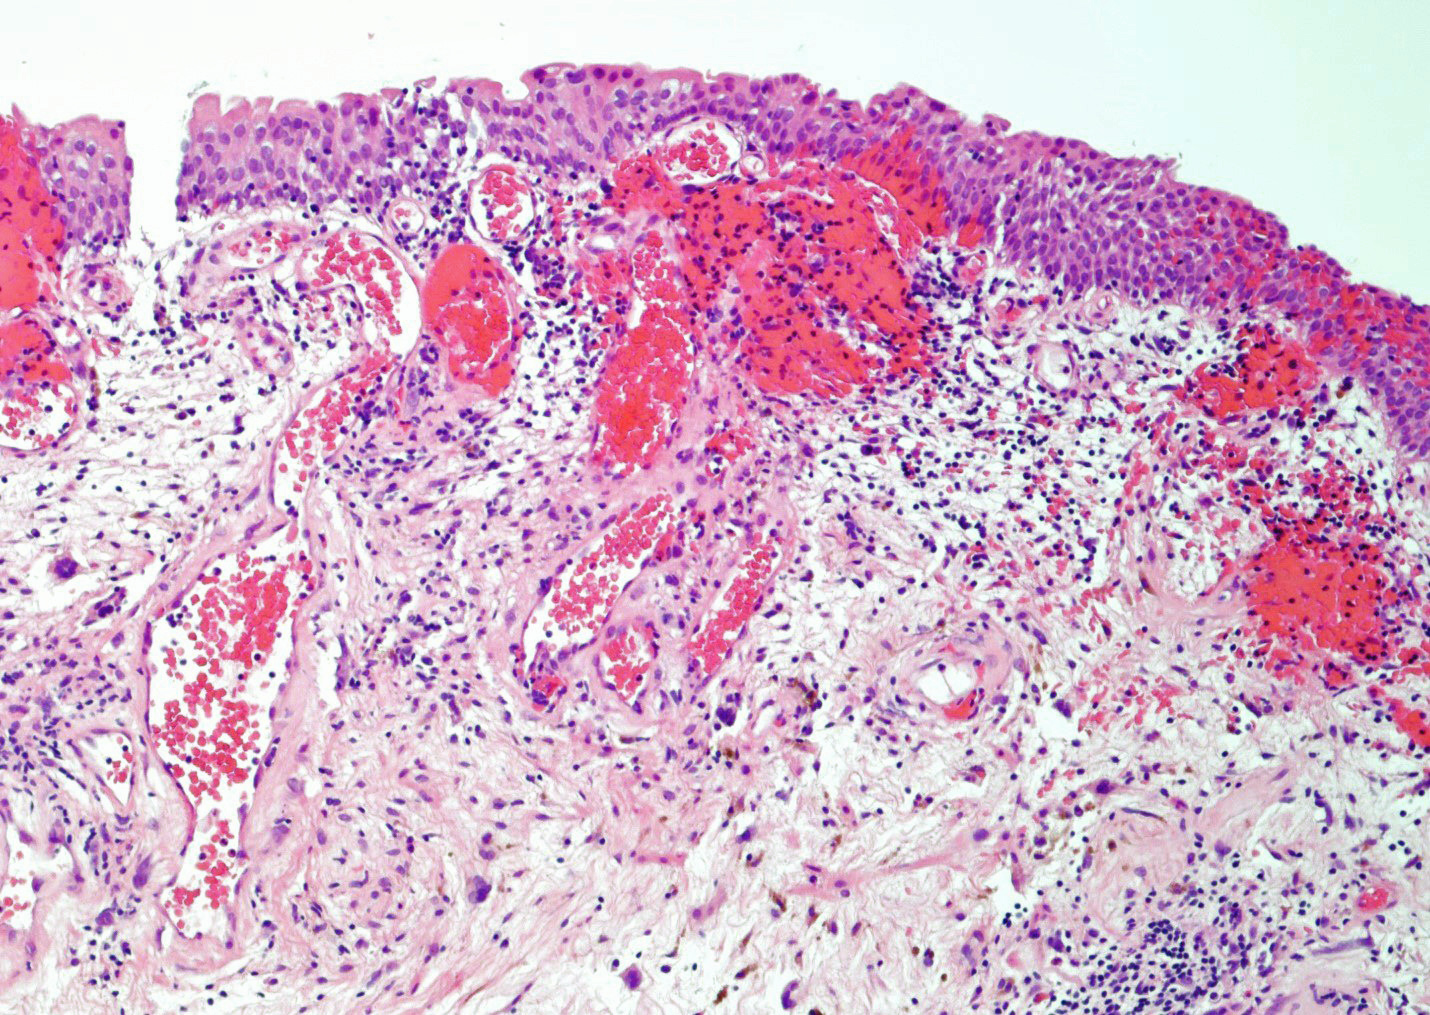

- Thickened bladder mucosal wall in acute phase and atrophy in chronic phase

- Bladder mucosa with marked congestion, hemorrhage, telangiectasia, ulceration, stricture and necrosis (Urol Int 2022;106:63)

- Vessels with fibrin thrombi, fibrinoid vascular necrosis, vascular congestion, thickened walls, endothelial proliferation and telangiectasia

- Acute and chronic inflammation

- Fibrosis and edema

- Hemorrhage and hemosiderin

- Acute phase: edematous, congested and telangiectatic vessels, acute and chronic inflammatory infiltrate, atypical stromal cells with multinucleated forms

Microscopic (histologic) images

Contributed by Y. Albert Yeh, M.D., Ph.D. and Jennifer Lee, M.D.